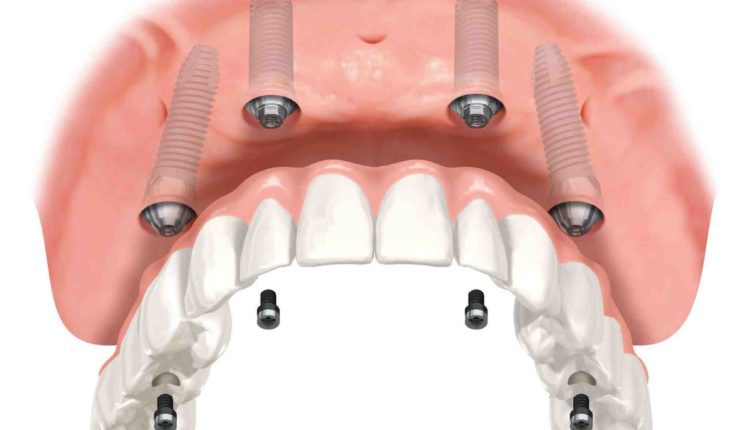

How many implants are needed for full mouth?

For example, a full-mouth dental implant procedure – often referred to as full-mouth crown and bridge implants – may require 12 to 16 dental implants or six to eight implants for the upper jaw and six to eight implants for the upper jaw. lower jaw.

How many implants are needed for a complete dentition? In general, implant prostheses used for complete tooth replacement on the upper or lower dental arch require only a few dental implants to successfully and comfortably stabilize the prosthesis. For some patients, two to four dental implants are sufficient. For others, six or more implants may be required.